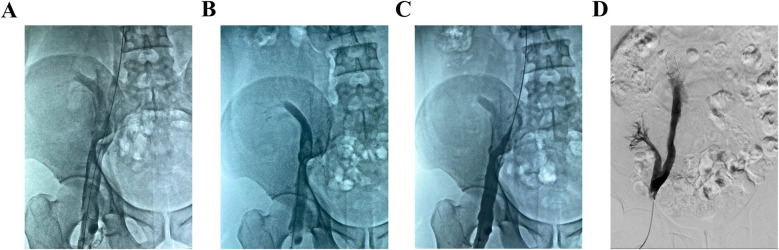

下肢深静脉血栓(DVT)合并移植肾静脉血栓形成是一种罕见而复杂的静脉血栓栓塞,可导致移植肾静脉阻塞。这种情况导致肾脏实质水肿,最终损害移植器官的功能。它是肾移植后的灾难性并发症,可能导致移植肾功能丧失和手术失败。治疗的主要目的是及时清除移植肾静脉中的血栓,从而尽快恢复正常的静脉回流和肾功能,提高患者预后。目前,手术取栓和溶栓治疗被认为是主要的治疗方式。外科取栓术通常被推荐为一线治疗方法,因为它能快速清除血栓。迄今为止,关于使用AngioJet取栓系统治疗DVT合并移植肾静脉血栓的文献有限。在此报告中,我们报告两例中年男性患者诊断为急性下肢深静脉血栓合并移植肾静脉血栓。两例患者分别在15年和4年前接受了异基因肾移植。在这些病例中,我们采用AngioJet取栓系统进行急诊血栓抽吸治疗。两例患者下肢深静脉及各自移植肾静脉内的血栓均被完全清除。随后,两例患者尿量逐渐增加;此外,肾功能逐渐改善到可接受的范围。值得注意的是,在随访评估中,患者均未出现术后并发症,也未出现血栓复发。

Lower extremity deep venous thrombosis (DVT) combined with transplanted renal vein thrombosis represents a rare and complex form of venous thromboembolism that leads to obstruction of the transplanted renal vein. This condition results in parenchymal edema of the kidney, ultimately impairing the function of the transplanted organ. It constitutes a catastrophic complication following renal transplantation, potentially resulting in loss of function of the transplanted kidney and failure of the surgical procedure. The primary objective of treatment is to promptly remove thrombi from the transplanted renal vein, thereby restoring normal venous return and renal function as swiftly as possible to enhance patient prognosis. Currently, surgical thrombectomy and thrombolytic therapy are considered the mainstay treatment modalities. Surgical thrombectomy is generally recommended as a first-line approach due to its efficacy in achieving rapid thrombus removal. To date, there exists limited literature regarding the utilization of the AngioJet thrombectomy system for managing DVT in conjunction with transplanted renal vein thrombosis. In this report, we present two cases involving middle-aged male patients diagnosed with acute lower extremity DVT complicated by transplanted renal vein thrombosis. Both patients had undergone allogeneic kidney transplantation 15 and 4 years prior, respectively. In these instances, we employed the AngioJet thrombectomy system for emergency thrombus aspiration treatment. The thrombi within both patients' lower extremity deep veins and their respective transplanted renal veins were completely removed. Subsequently, urine output gradually increased for both patients; moreover, their renal function progressively improved to an acceptable range. Notably, neither patient developed postoperative complications nor exhibited any recurrence of thrombi during follow-up evaluations.